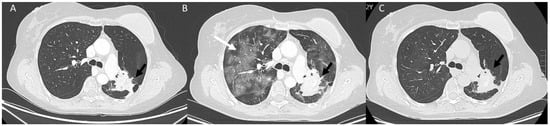

- Fusco, R.; Simonetti, I.; Ianniello, S.; Villanacci, A.; Grassi, F.; Dell’Aversana, F.; Grassi, R.; Cozzi, D.; Bicci, E.; Palumbo, P.; et al. Pulmonary Lymphangitis Poses a Major Challenge for Radiologists in an Oncological Setting during the COVID-19 Pandemic. J. Pers. Med. 2022, 12, 624. [Google Scholar] [CrossRef] [PubMed]

- Kalisz, K.R.; Ramaiya, N.H.; Laukamp, K.R.; Gupta, A. Immune Checkpoint Inhibitor Therapy-related Pneumonitis: Patterns and Management. Radiographics 2019, 39, 1923–1937. [Google Scholar] [CrossRef] [PubMed]